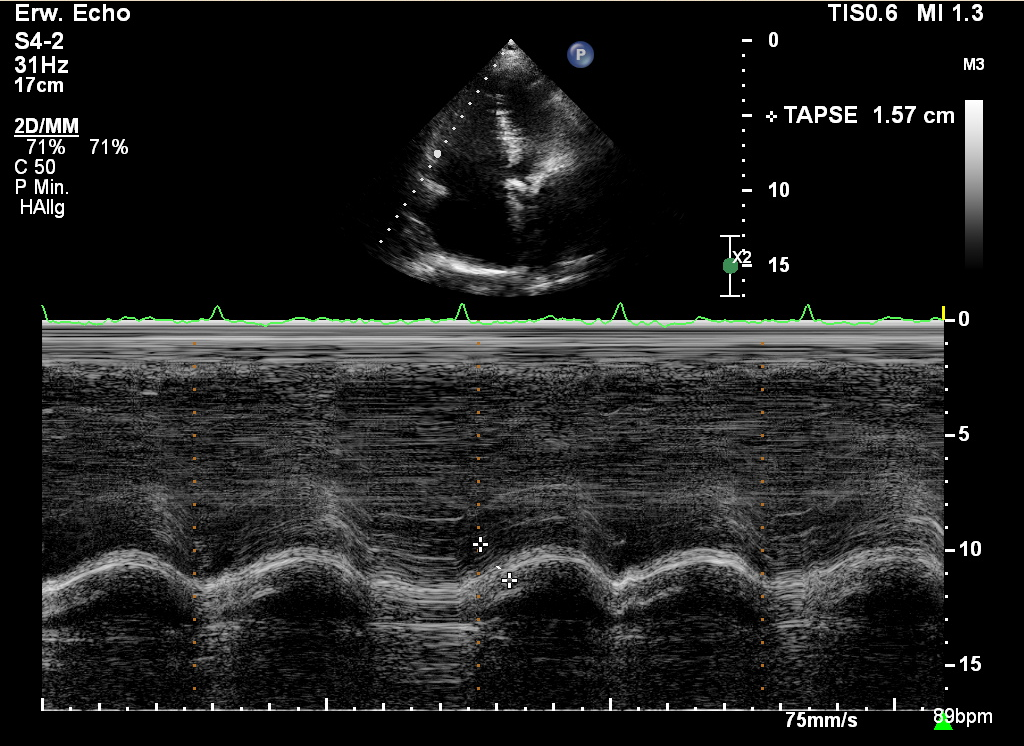

M-Mode

Der M-Mode zeigt die Bewegungsabläufe von Strukturen und Organen. Er hat an Bedeutung verloren, ist aber in bestimmten Situationen wertvoll.

Vorteil des M-Mode

• hohe zeitliche Auflösung

• ermöglicht die Messung von Zeitintervallen

• für bestimmte Messungen günstig

heutiger Einsatz des M-Mode

• TAPSE

• AVPD (=MAPSE)